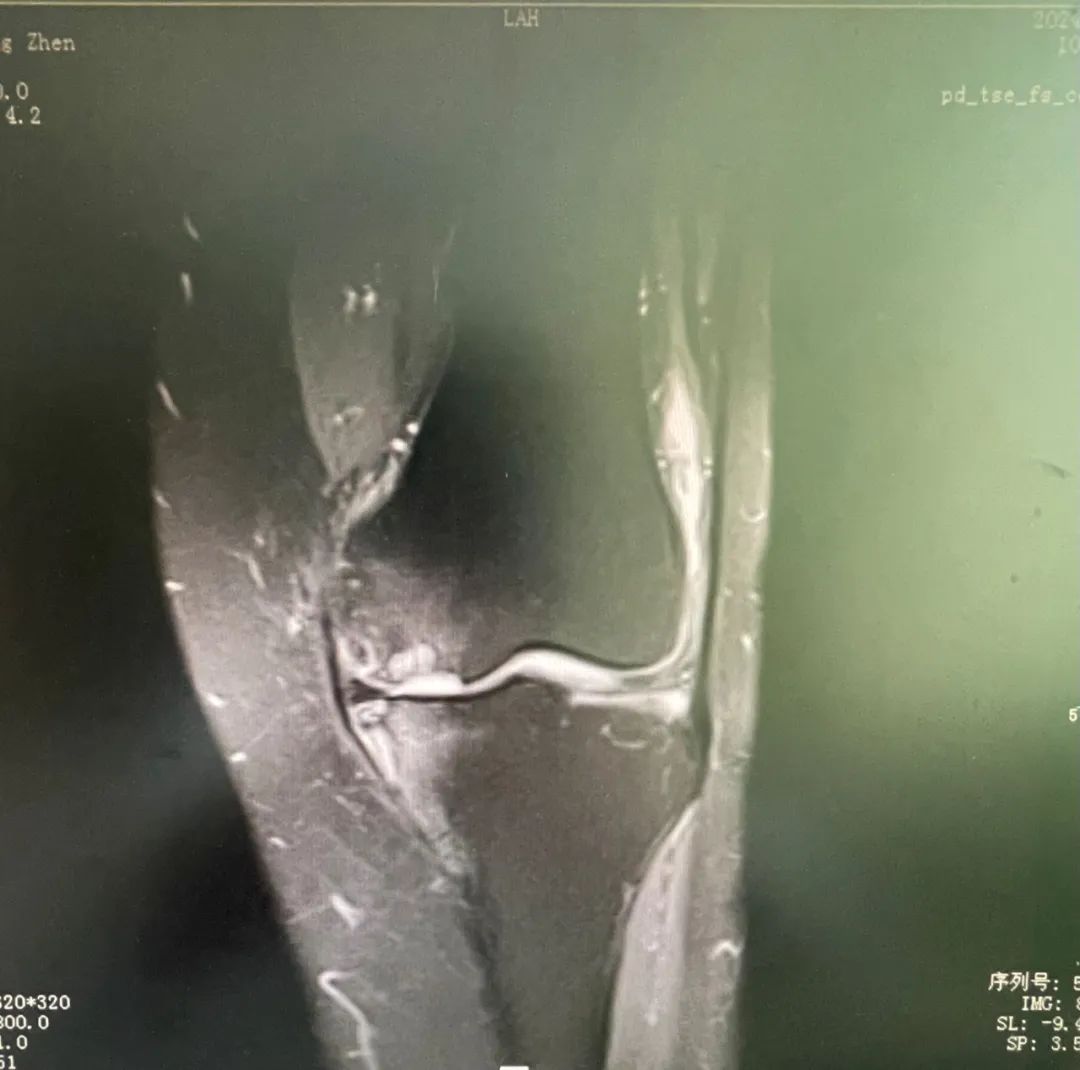

膝关节疼痛背后的真相 术前检查片 老年膝关节疼痛通常被认为是由于骨头磨损所致,但实际情况可能更为复杂。例如,73岁的梁大姐就经历了这种痛苦。她的症状包括走路困难、关节肿胀和持续的疼痛。经过详细的检查和诊断,医生发现梁大姐患有膝关节内侧自发性骨坏死,这是一种不常见的疾病。这种病症涉及到软骨的退变、软骨下骨的水肿以及骨头的坏死,这些因素共同导致了剧烈的疼痛。 单髁置换术——治疗新选择 针对梁大姐的情况,ky骨科一区的许国胜主任提出了三种手术方法:关节镜手术、全膝关节置换术和单髁置换术。考虑到创伤大小、术后恢复速度和功能恢复等因素,最终选择了单髁置换术。这种手术仅更换受坏死影响的内侧间室骨头,同时保留了外侧间室、髌股关节和交叉韧带的正常功能。与传统全膝关节置换相比,单髁置换具有创伤小、疼痛轻、恢复快等优点。 术后效果与快速康复 梁大姐在接受了内侧单髁置换术后,第二天就能下地走路,并在术后第三天出院回家。一个月后复查时,她的左膝关节内侧疼痛症状完全消失,关节活动自如。这一案例证明了单髁置换术的有效性。此外,该手术在国外已有超过30年的历史,在国内外也有超过15年的应用时间,技术成熟且效果稳定可靠。对于早期病变的患者来说,单髁置换术不仅能明显改善生活质量,还能延缓全膝置换的时间。